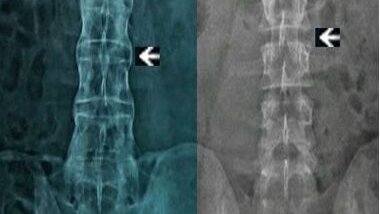

Анкилозирующий спондилит /АС/ (Болезнь Бехтерева /ББ/) - это хроническое воспалительное заболевание с поражением крестцово-подвздошных сочленений (обязательно), позвоночника, суставов, глаз, энтезисов, внутренних органов (опционально). К сожалению, выявляется не всегда своевременно, к ревматологу попасть трудно, а что-то спросить нет времени, поэтому, я думаю, будет не лишним ответить на те вопросы, которые волнуют самих пациентов (можете продолжать их оставлять в комментариях). *Часть вопросов была задана в самом интересном ТГ-канале про ревматологию...

Анкилозирующий спондилоартрит или болезнь Бехтерева - это хроническое полисистемное воспалительное заболевание, поражающее преимущественно крестцово-подвздошные суставы и осевой позвоночник. Полисистемное заболевание означает, что болезнь может затрагивать не только позвоночник и суставы. Про это мы будем говорить ниже. Данную статью я буду обновлять со временем. Прогноз у пациентов с болезнью Бехтерева лучше, чем при ревматоидном артрите. Кого поражает болезнь Бехтерева? Болезнь Бехтерева затрагивает 0,1-1% населения...